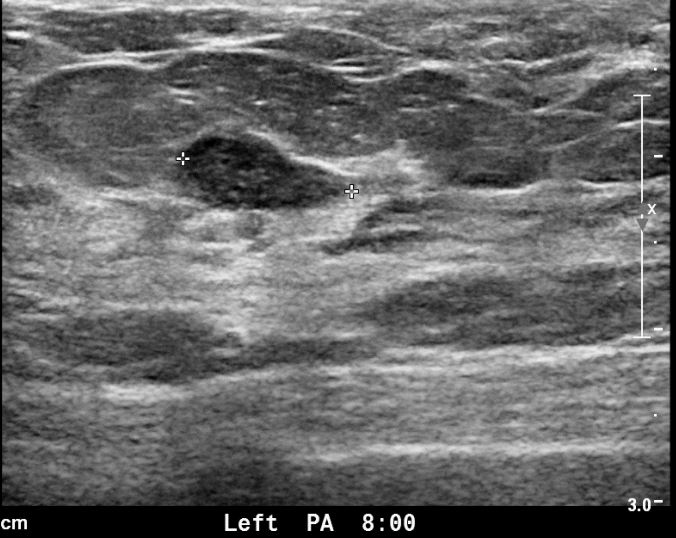

아산유외과 개원후 628번째 유방암진단

상기 환자 외부검사상 이상소견으로 내원하신 40대 여성으로 양측에 의심스러운혹있어 MMT 시행후 양측 유방암 진단되었습니다.